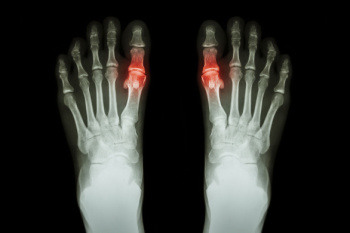

Symptoms of gout are warmth, swelling, discoloration, and tenderness in the affected joint area. The small joint on the big toe is the most common place for a gout attack to occur.

Diagnosis for gout is done by checking the level of uric acid in the joints and blood. Your podiatrist may also prescribe medicine to reduce uric acid buildup in the blood, which will help prevent any gout attacks.